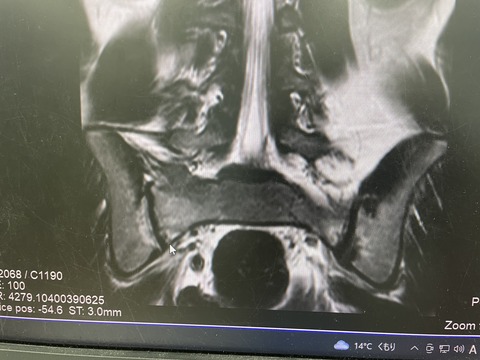

成長期は分離症が多いですよね

本日、勉強会の後、

午後の診療だけでも、3人の分離症の患者様が来られました

その中で、16歳での、分離サインがあり、

年齢的に、発症はないと考えておりましたが、

痛みが強すぎるため分離症を疑い、

MRIとCTを取りました、

IMG_6417

時々ありますが、仙骨の疲労骨折と言うものもあります、

実際に分離症との鑑別は大事ですね